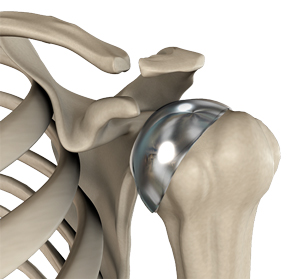

• Partial Shoulder Replacement

Img-Partial Shoulder Replacement

Partial shoulder replacement, also called shoulder hemiarthroplasty, is a surgical procedure...